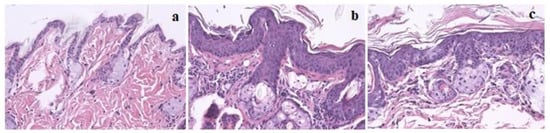

Histological analysis of skin chest and ear samples are reported in Table 2. P. umbilicalis-supplemented-diet group II showed epidermal hyperplasia in 100% of the mice, while base diet-fed group IV only showed 36.4% of epidermal hyperplasia. Therefore, there were statistically significant differences concerning the skin chest among supplemented and not supplemented animals (p = 0.004). On the other hand, the P. umbilicalis-supplemented-diet group II mice did not show epidermal dysplasia, while 63.6% of non-supplemented mice showed epidermal dysplasia. Regarding ear samples results, there were no statistically significant differences between the supplemented and the non-supplemented groups. Figure 1 shows skin histological samples for (a) normal skin, (b) epidermal hyperplasia, and (c) epidermal dysplasia. On histological analysis, all mice showed normal hepatic morphology (data not shown).

Figure 1.

Skin histology samples of female FVB/n mice, magnification 200×, hematoxylin and eosin (H&E) staining: (a) Normal skin histology in wild-type groups (I and III); (b) Epidermal hyperplasia in K14human papillomavirus(HPV)16 transgenic mice; (c) Epidermal dysplasia in K14HPV16 transgenic mice.

The left ear was collected and longitudinally sectioned for histological analysis. Chest skin was harvested from the lower cervical to the diaphragmatic zone, forming a square of approximately 1 cm2. Skin samples from the chest and ear and liver samples were fixed in 10% neutral buffered formalin and processed for hematoxylin and eosin (H&E) staining to classify HPV-induced cutaneous lesions and any toxic hepatic lesions attributable to P. umbilicalis. Skin samples were classified as normal, epidermal hyperplasia, or epidermal dysplasia. Normal epidermis was characterized by the presence of only 1 or 2 cellular layers and a keratin layer, while hyperplastic and dysplastic lesions showed over 3 cellular layers. Additionally, dysplastic lesions showed marked nuclear pleomorphism and suprabasal mitotic figures. Liver samples were classified as normal liver, grade I hepatitis, grade II hepatitis, and grade III hepatitis, as previously described [].